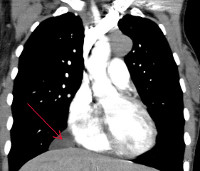

Стандартный алгоритм обследования пациентов с целомической кистой перикарда включает обязательную рентгенологическую диагностику: рентгеноскопию и рентгенографию грудной клетки, рентгеноскопию сердца с контрастированием пищевода. Рентгенологически целомическая киста перикарда определяется как шаровидная или овальная тень, обычно локализующаяся в кардиодиафрагмальном синусе. Наружный контур тени четкий, внутренний обычно сливается с тенью сердца, а нижний - с тенью диафрагмы. Характерно наличие передаточной пульсации. Раньше для диагностики целомических кист перикарда широко использовалась пневмомедиастинография, однако на современном этапе ее успешно заменила КТ грудной клетки.